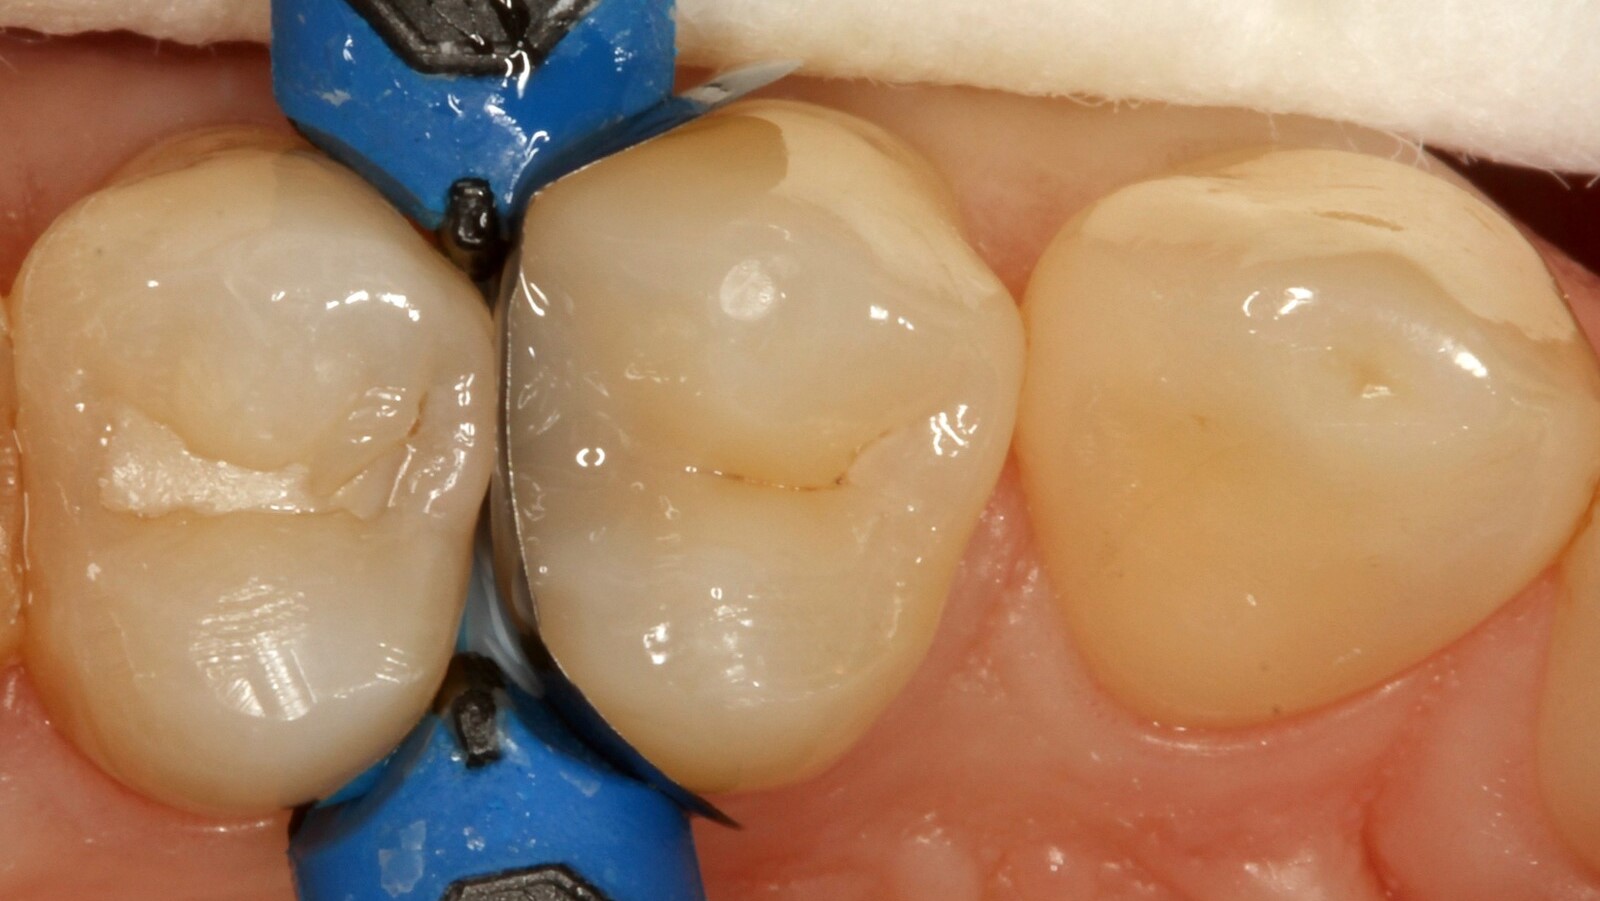

Professor Ernst first identified the hidden caries and opened the carious lesion to show the patient the problem (Fig. 1-2). He then excavated the caries, prepared the cavity and placed a sectional matrix (Fig. 3) before sealing the cavity with adhesive (Fig. 4). In a single step, he filled the cavity with Venus Bulk Flow ONE (Fig. 5). Once the restoration was completed, Prof. Ernst polished it (Fig. 6) and took a control radiograph, which also shows the excellent radiopacity of Venus Bulk Flow ONE (Fig. 7).